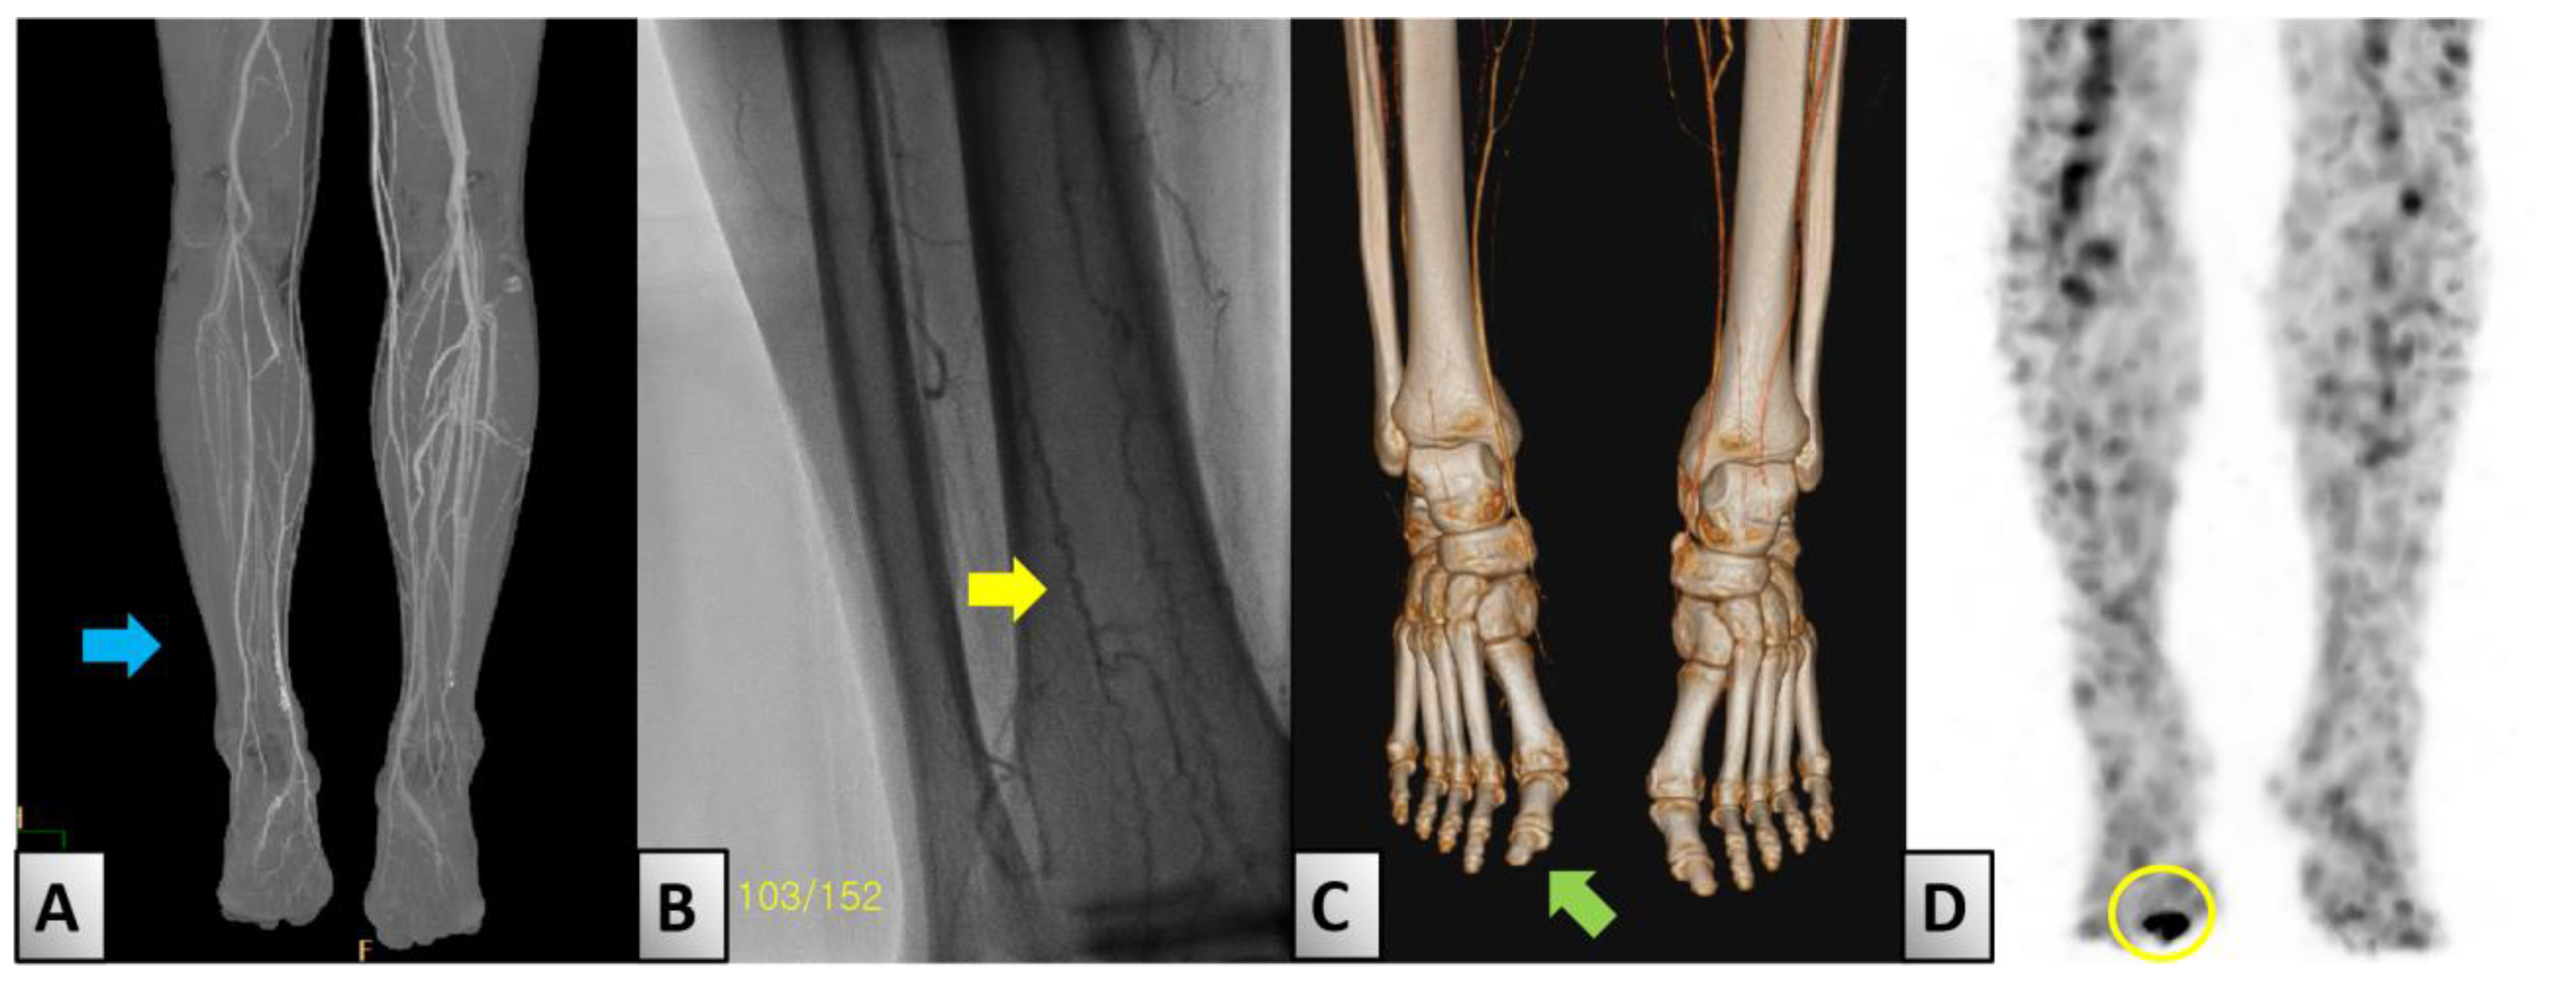

| 21 April 2022 | Lower-extremity ct | Focal thrombus identified in right popliteal artery and distal ATA. |

| 4 May 2022 | Right femoral arteriography | Severe stenosis in right popliteal artery; chronic total occlusions in right ATA, right posterior tibial artery (PTA), and right peroneal artery Corkscrew findings suggestive of Buerger’s Disease. |

| 12 May 2022 | Right popliteal–tibioperoneal artery bypass surgery with GSV. | Surgical intervention to bypass identified thrombus, using GSV. |